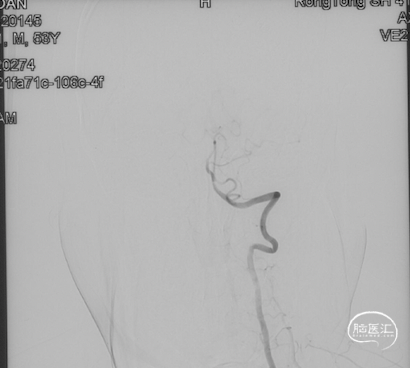

R-ICA正侧位见右侧脑膜垂体干向瘘口供血

L-ICA正侧位见左侧脑膜垂体干分支向瘘口供血

L-ECA正侧位未见向瘘口供血

L-VA、R-VA正侧位右侧小脑上动脉脑膜支向瘘口供血

结构分析:右侧天幕区硬脑膜动静脉瘘,瘘口位于右侧岩上窦,供血动脉主要包括右侧脑膜中动脉的颞支、岩鳞支,右侧枕动脉分支,右侧颞浅动脉分支,双侧脑膜垂体干,右侧小脑上动脉脑膜支,经幕上迂曲扩张的静脉、中脑周围静脉、基底静脉向深部静脉引流,引流静脉起始部见扩张的静脉球。Cognard分型IV型,Borden分型III型,Lawton分型IV型(岩上窦型)。

手术策略:左侧脑膜中动脉粗大、平直,经由该血管可以接近瘘口,因此首选经右侧脑膜中动脉入路栓塞。